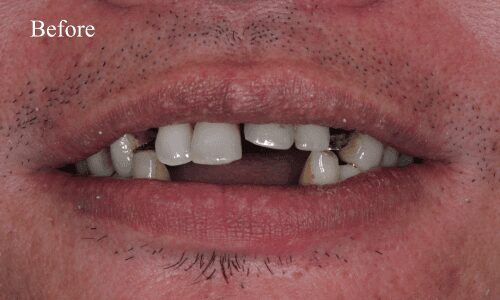

Full Mouth Rehabilitation

Full mouth rehabilitation or FMR is a restorative dental procedure which involves replacing all the teeth in the upper and lower jaws.This is a comprehensive treatment that combines general, cosmetic and restorative dentistry. This means you may have to get dental crowns, implants and whitening done at the same time to bring back the original strength, functionality, and aesthetic appeal of your teeth.